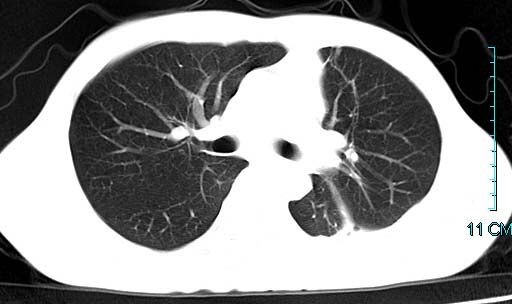

以下是引用qian在2006-3-28 14:32:00的发言:[br]左肺下叶大片状阴影,密度不均,见有条片影和空洞及气液平,少量胸腔积液伴有胸膜增厚,从图像看积液密度比水的密度高,结合病史,考虑左下肺化脓性炎症伴有脓胸。

以下是引用wawaquan在2006-3-28 22:25:00的发言:[br]左上肺舌段多发斑片影。结合“男24y咳嗽咳痰气促伴高热(38.5--39.5)20多天”及穿刺史,[br]考虑1 左下肺化脓性炎症;2脓胸。

以下是引用乡医在2006-3-28 18:37:00的发言:[br]左侧多发液气平面结合患者男24y咳嗽咳痰气促伴高热(38.5--39.5)20多天,查胸水:ldh239.3,总蛋白59.19,tb-ab阴性,利凡它试验+,红c2.7*109,白c1.08*109,分类淋巴92%分叶8%,考虑1脓胸2肺隔离征感染